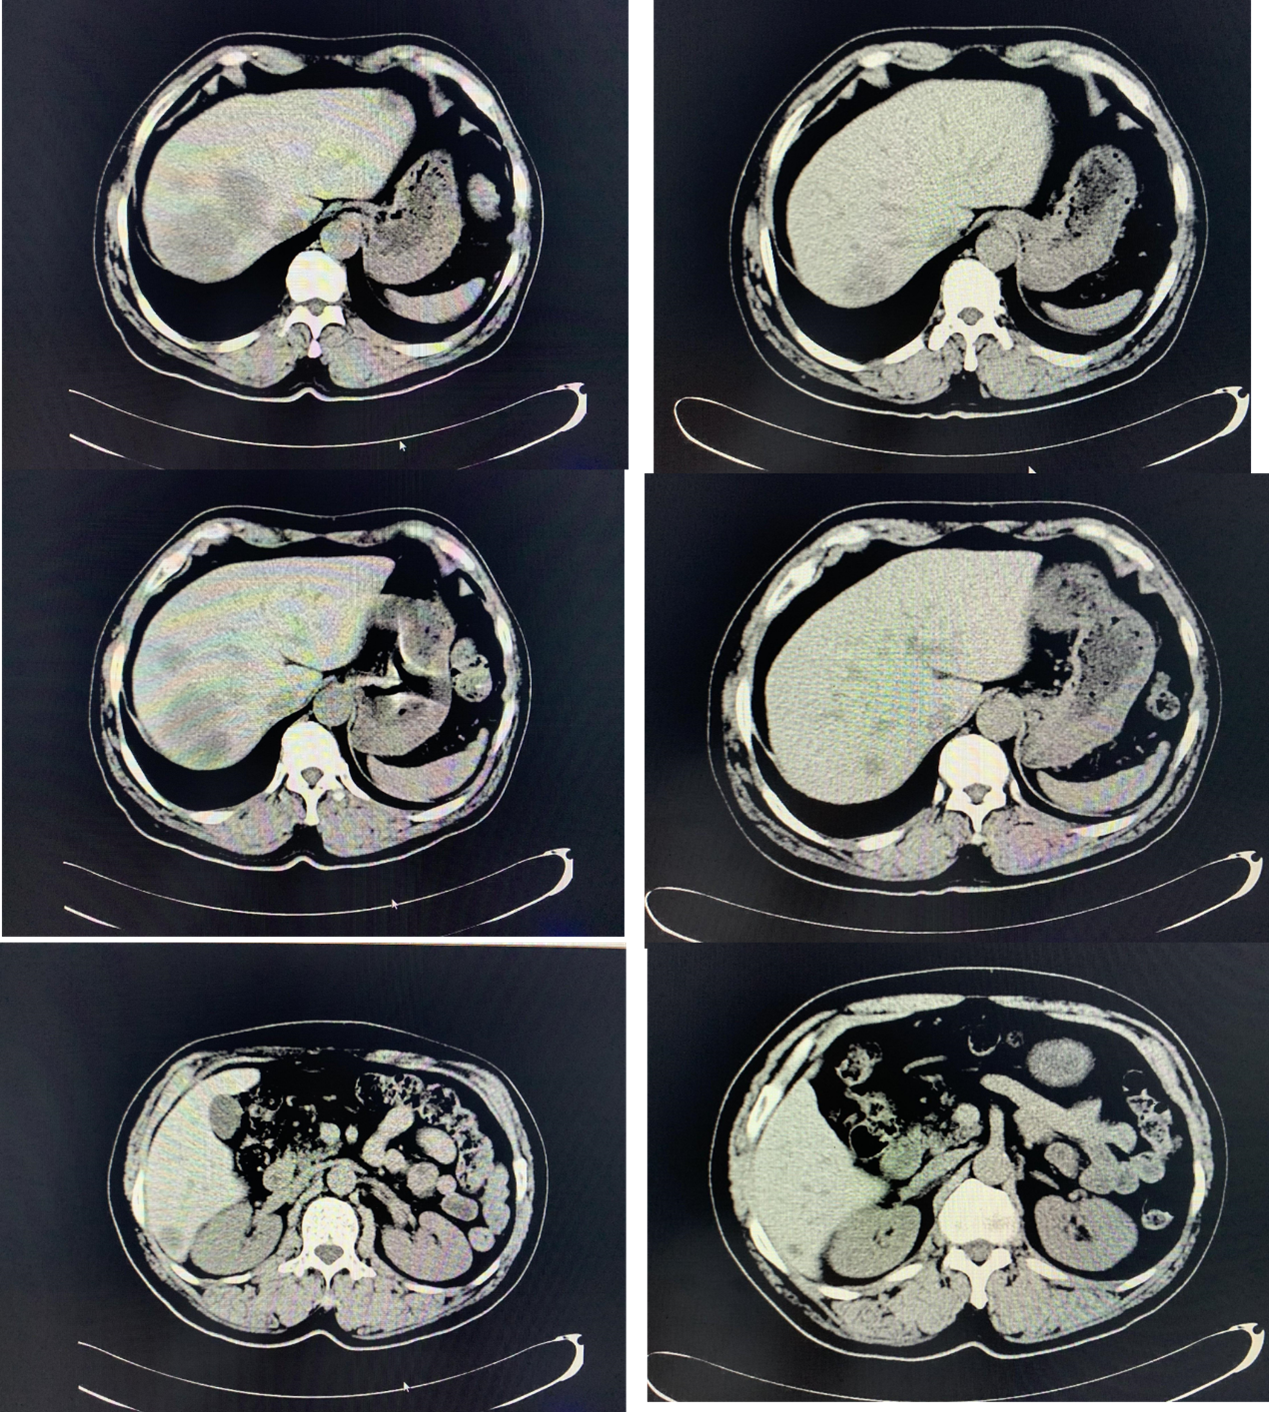

2021-11-26,行CT平扫,示乙状结肠壁增厚形成肿物,考虑乙状结肠癌可能性大;请结合临床及MRI助诊;肝脏多发结节肿物,考虑转移可能性大;腹腔、腹膜后、肠周及盆腔内多发淋巴结,转移可能性大;纵膈多发淋巴结,性质待定,考虑炎性可能性大,转移待排;颅脑及颈部未见明确异常。

图1. 2021-11-26平扫CT

图4. 平扫CT对比:2021-11-26(左)与2022-3-8(右)

2022-3-12至2022-5-8,行第5-8周期西妥昔单抗+FOLFOXIRI治疗。

图9. 平扫CT对比:2023-1-29(左)与2023-3-28(右)

图10. 平扫CT对比:2023-7-13(左)与2023-10-12(右)

图11. 2023-12-15 平扫CT